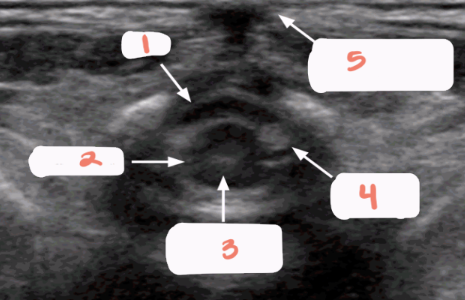

1

subarachnoid space

2

cartilaginous spinous processes

3

dura mater

4

epidural space

5

central echo complex in hypoechoic spinal cord